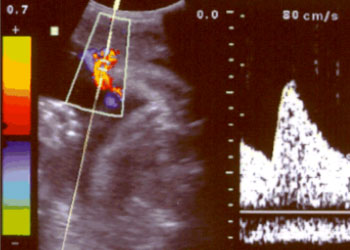

Ejemplos de ecografías del embarazo